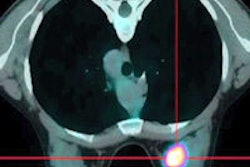

In the second study, researchers from Hôpital Saint-Louis in Paris prospectively evaluated 20 patients with triple-negative breast cancer who received chemotherapy before scheduled surgery.

The participants underwent PET imaging with F-18 FDG at the start of chemotherapy and again after the second cycle of treatment to determine metabolic changes in tumors during therapy. At the point of surgery, the scans indicated that therapy was completely successful in six patients, while 14 others were found to have remaining tumors.

Patients with less than a 42% decrease in metabolism of the agent after two cycles of chemotherapy still had some residual cancer after treatment and were therefore at high risk of early relapse, the researchers concluded.

"Interim [F-18 FDG-PET/CT] could become a major tool for early response assessment of this aggressive cancer, similar to the role that [F-18 FDG] plays in assessing aggressive lymphomas," said Dr. David Groheux, a principal researcher in the department of nuclear medicine.